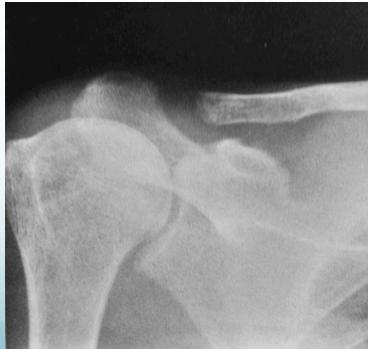

- Lateral end of clavicle

- Lateral end of clavicle resorption